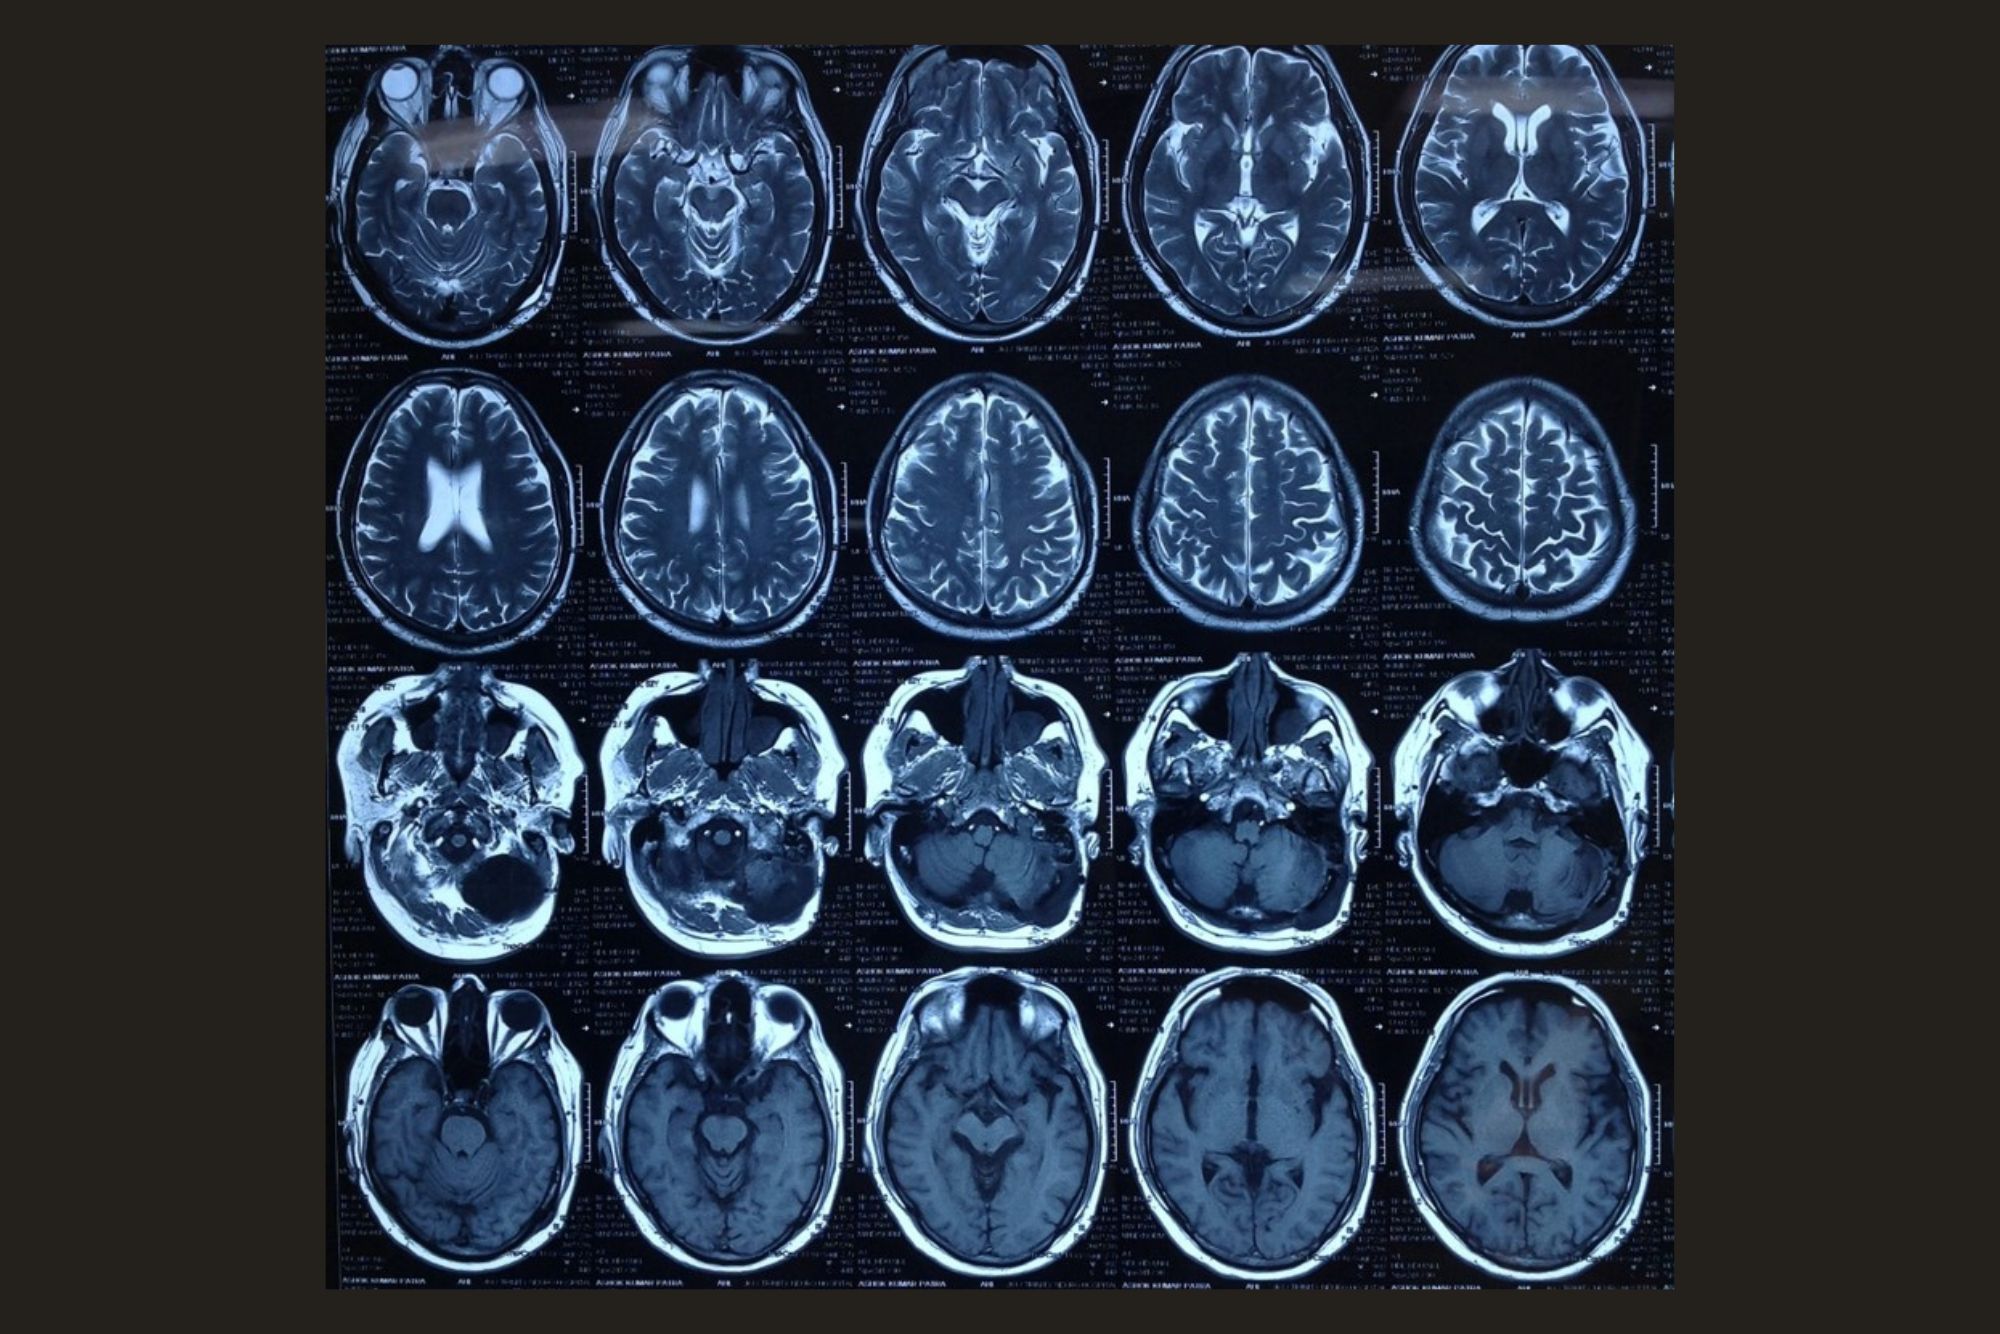

Grade II Glioma

Preoperative MRI

28 yr. Gentleman presenting with single episode of GTCS

No Neurological deficits

1 year Post operative contrast MRI